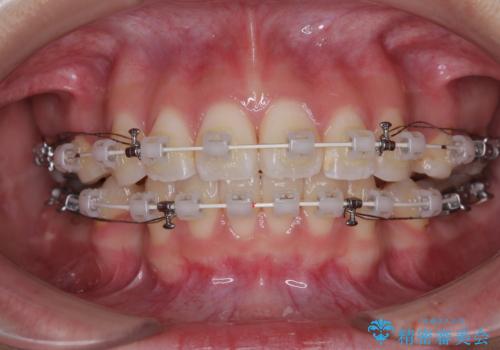

- 矯正装置

- 審美装置

- 前歯が突出して、眠るときに口が開いてしまうことを気にして来院された患者様です。

横から見た際の口元の飛び出した印象も改善したいとのことで、上下左右の第一小臼歯4本を抜歯し、ワイヤー装置にて抜歯矯正を行うこととしました。